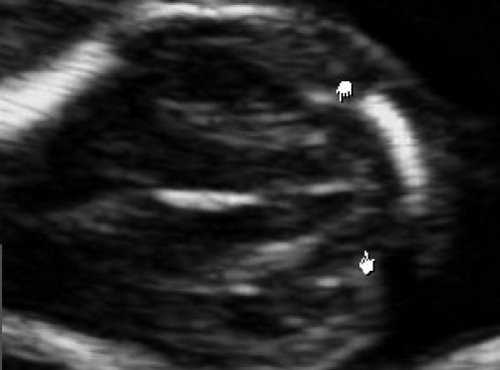

В наблюдениях 1-3 имело место расширение боковых желудочков до 14, 18 и 32 мм соответственно (рис. 5), 3-го желудочка - до 3,2 и 4,9 мм и отсутствие картины полости прозрачной перегородки (ПП). При этом в наблюдениях 2 и 3 отмечалось также нарушение срединных структур мозга и слияние лобных рогов. Мозолистое тело было выявлено в наблюдении 2, что было констатировано по наличию его артерии (рис. 2.1).

Рис. 5. Аксиальные срезы головного мозга. Показано расширение боковых желудочков мозга при полной форме РЭС и картина серпа мозга.

б) Наблюдение 2, 3D.